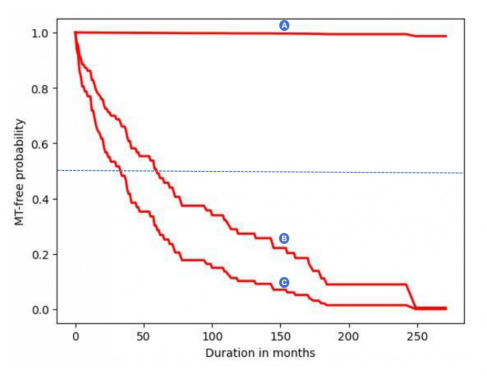

使用平台預測病變風險,需輸入二十六項有關病人的個人背景資料、病症的臨床和病理描述,以及接受的治療等。就每個個案的風險評估,平台會呈現一條曲線,展示每個時間點預測的風險級別。而當患者達到一定的風險水平時,醫護人員可開始加密對患者的監察。(圖一)

而預測的風險水平,從輸入資訊日起計17年内維持準確度。值得注意的是,預測的風險曲線會隨著輸入數據的轉變而有所變化,例如吸煙和飲酒狀況、受影響的口腔部位、接受的治療、復發情況以及治療監測期間口腔上皮變異的程度等,因此輸入數據需適時更新。